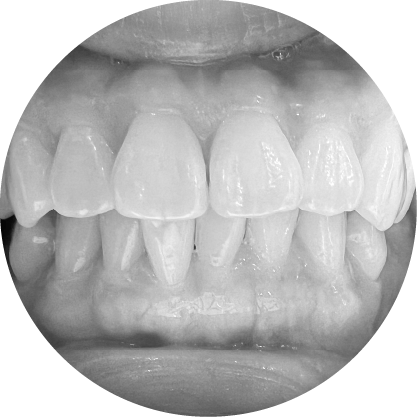

ตัวอย่างในชีวิตจริง

Underbite teeth illustration – lower teeth in front

ฟันล่างยื่น (รีเวอร์ส โอเวอร์เจ็ต)

การแก้ไขฟันสบล่าง เพื่อความมั่นใจและการใช้งานที่มีประสิทธิภาพ

ฟันสบล่างคือภาวะที่ฟันล่างยื่นออกมามากกว่าฟันบน ซึ่งมักส่งผลต่อการเคี้ยวอาหารและความสมดุลของใบหน้า การจัดฟันสามารถช่วยปรับแนวขากรรไกรให้ถูกต้อง ช่วยเพิ่มทั้งประสิทธิภาพในการใช้งานและความสวยงามของใบหน้า